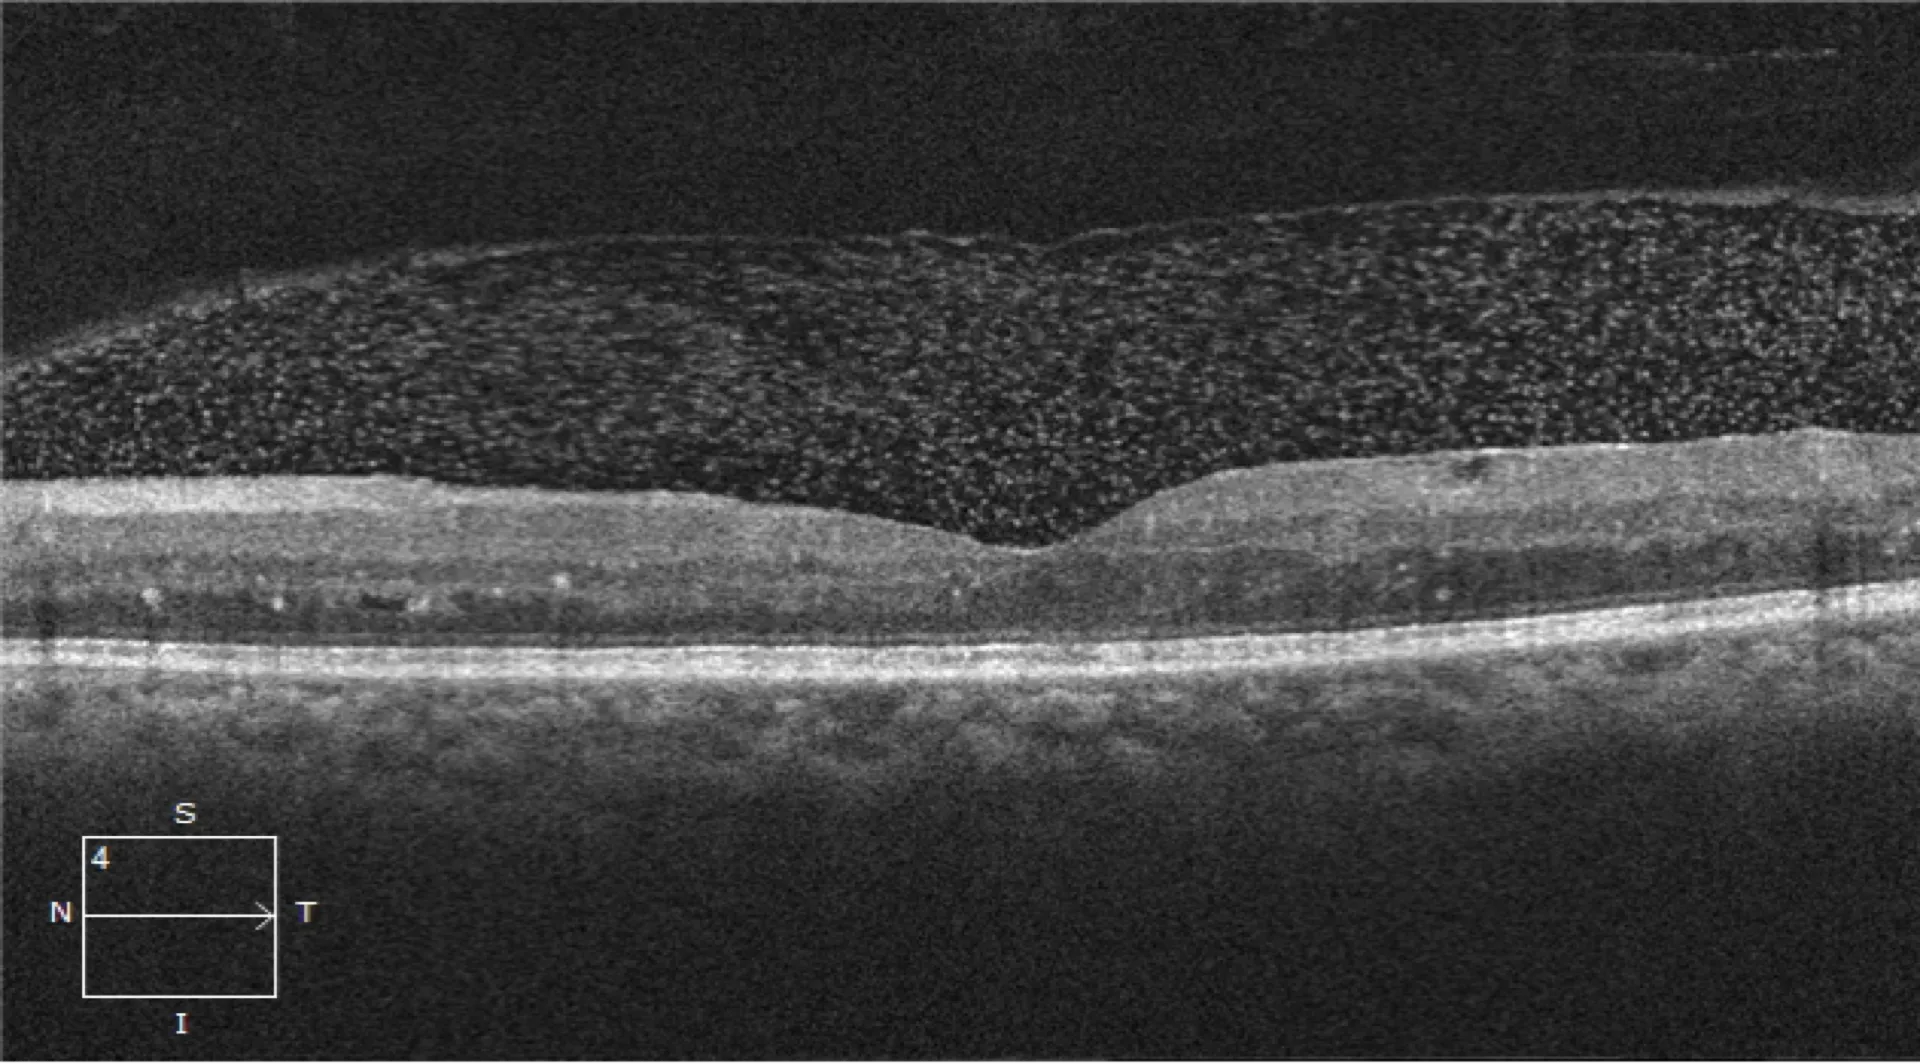

• Advanced OCT & imaging training

Fellows are trained in advanced diagnostic modalities (OCT, FA, ICGA, widefield imaging, OCT angiography) and get hands-on experience with retinal lasers, intravitreal injections, and opportunities to assist or perform vitrectomies under expert guidance.

• Principles of fundus photography, OCT, FFA, and OCT-A

• Hands-on practice in performing and interpreting retinal imaging

• Case-based interpretation of normal and abnormal scans

• Hands-on experience with OCT/OCTA interpretation

• Multimodal imaging in macular disorders (OCT, FA, OCTA)

• Hands-on interpretation of imaging in maculopathies

• Independent OCT interpretation exercises under faculty guidance

• Diagnostic skills & interpretation: Interpretation of advanced retinal imaging modalities like OCT, OCT-A, FFA, B-scan.